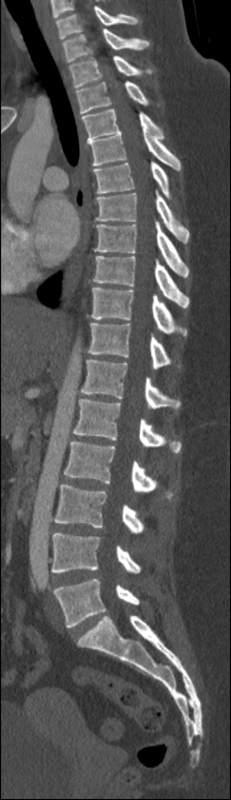

We trained and evaluated the method with five sets of CT and MR scans that visualize the spine. Reference segmentation masks for four of these datasets are publicly available, which allowed for a comparison with other publications that used the same data. Examples of images from the datasets are shown in Figure 3.

The thoracolumbar spine CT dataset consists of 15 dedicated spine CT scans that visualize all thoracic and lumbar vertebrae. It was originally used for the spine segmentation challenge held in conjunction with the Computational Spine Imaging (CSI) workshop at MICCAI 2014 (Yao et al., 2016). All subjects were young adults ( years) without vertebral fractures who were scanned with IV-contrast administration. The scans were reconstructed to in-plane resolutions of and slice thicknesses of . Semi-automatically obtained reference segmentations were provided by the challenge organizers. To allow for a comparison with the challenge results, we used the same data split with 5 scans for evaluation and the remaining 10 scans for training and development.

Similar performance was achieved for vertebra segmentation in various CT datasets with an average Dice score of and for vertebral body segmentation in an MR dataset with an average Dice score of . Surface distances were lower on CT images compared to MR images ( vs. ), however, there were also fewer training scans available in the MR dataset. Figure 4 illustrates the magnitude of differences of the automatic segmentations from the ground truth segmentations.

In the CT datasets, the segmentation was more accurate on high-resolution dedicated spine scans of healthy subjects compared with low-dose low-resolution chest CT scans and scans of subjects with in some cases severe compression fractures. This is also visible in the segmentation performance stratified by vertebra (Figure 5). Segmentations were more accurate for the lumbar (L1-L5) than for the thoracic vertebrae (T1-T12), which are covered by the more challenging low-dose chest CT scans. Outliers among the lumbar vertebrae correspond to vertebrae from the xVertSeg.v1 dataset, which features a number of severely deformed lumbar vertebrae that are particularly challenging to segment.